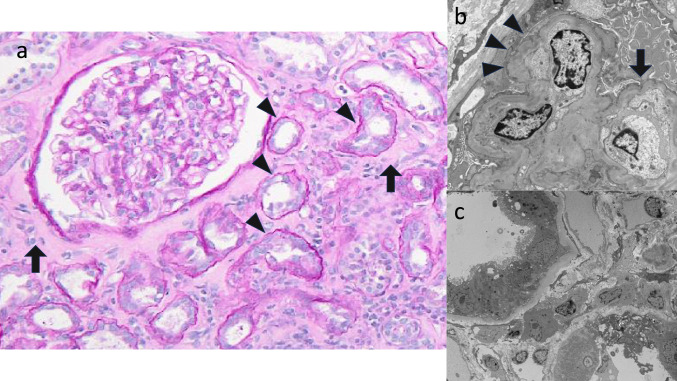

To date, the treatment strategy and long-term prognosis of acute kidney injury (AKI) after taking Benikoji CholesteHelp®, a red yeast rice supplement, remains unclear. We present three cases wherein renal dysfunction improved within a few months of supplement discontinuation, without immunosuppressive therapy. Case 1: A 59-year-old woman with a history of hypertension, treated with telmisartan (serum creatinine [sCr]: 0.65 mg/dL; estimated glomerular filtration rate [eGFR]: 71.3 mL/min/1.73 m2) and Benikoji CholesteHelp® for 7 months, developed Fanconi syndrome (FS) and severe renal impairment (sCr: 2.32 mg/dL; eGFR: 17.7 mL/min/1.73 m2). Renal biopsy and gallium-67 scintigraphy revealed no active drug-induced interstitial nephritis. Her condition improved significantly after supplement discontinuation. Her renal function gradually improved, with 3-month follow-up sCr and eGFR values of 0.96 mg/dL and 46.5 mL/min/1.73 m2, respectively; however, these were still worse than the pre-onset values. Case 2: A 48-year-old man had mild renal dysfunction (sCr: 1.12 mg/dL; eGFR: 56.76 mL/min/1.73 m2) after taking Benikoji CholesteHelp® for approximately 2 years; this was reversed upon supplement discontinuation. Case 3: A 47-year-old man with FS and mild renal dysfunction (sCr: 1.09 mg/dL; eGFR: 58.5 mL/min/1.73 m2) after taking Benikoji CholesteHelp® for approximately 4 months, showed notable improvement in FS after supplement discontinuation; however, the mild renal dysfunction persisted. The primary intervention in all cases was immediate supplement discontinuation, leading to rapid improvement in renal function, without need for immunosuppressive therapy. These findings increase our understanding of renal impairment caused by red yeast rice, with improvement after withdrawal, sometimes after several months.